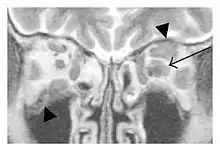

The extent of inflammation that can occur in IgG4-ROD is well demonstrated on magnetic resonance imaging (MRI).

![]() Bilateral supraorbital nerve enlargements (arrows) and right infraorbital nerve (arrow head) enlargement in a 47-year-old woman with a serum IgG4 of 1000 mg/dL.[1] (T1-weighted MRI) |